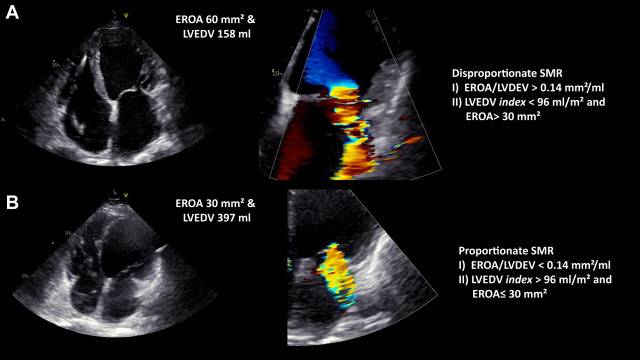

Eur Heart J Cardiovasc Imaging. 19: jeac136Brener M.I. Grayburn P. Lindenfeld J. et al.

Right ventricular-pulmonary arterial coupling in patients with HF Secondary MR: analysis from the COAPT trial.